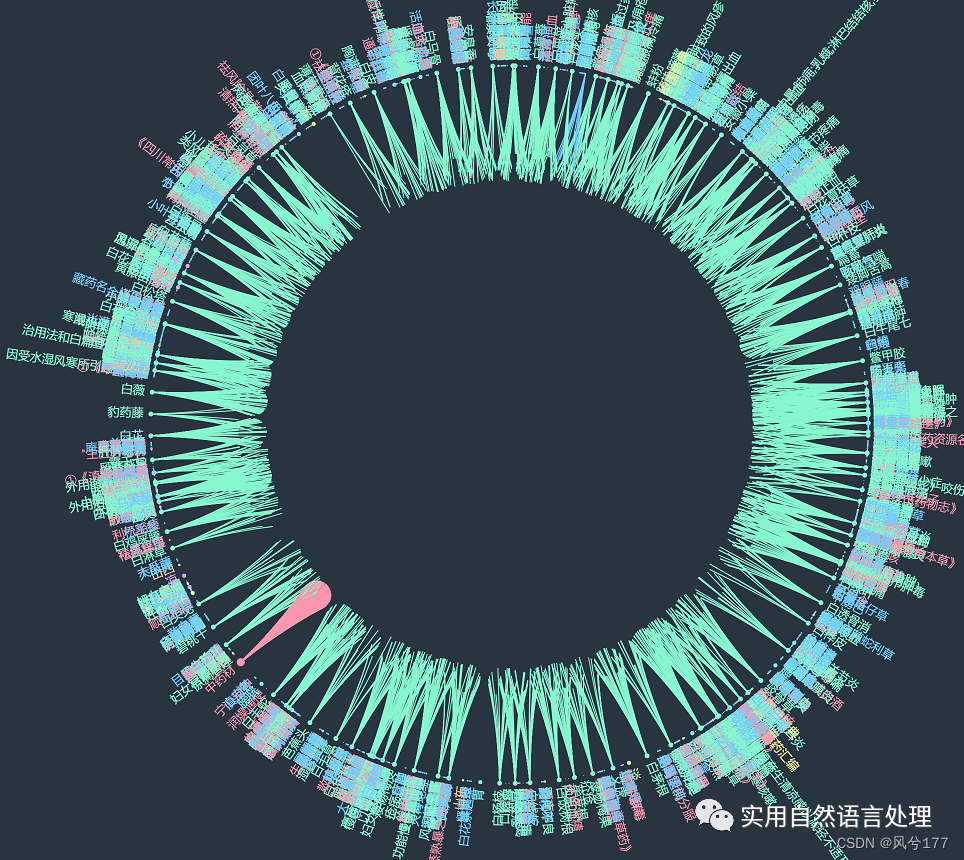

本文将基于pyecharts框架,对中药材知识图谱进行“力导图”和“环形分布”可视化,同时,对中药材地理分布、来源和别名关系进行分析与可视化。

2.2 中药材知识图谱可视化

前文自顶向下构建中药知识图谱初探已经介绍了中药材知识图谱的构建和neo4j可视化过程,接下来将对该图谱数据利用pyecharts进行可视化。

少量数据的中药知识图谱-环形图

少量数据的中药知识图谱-环形图(部分节点展示图1)

少量数据的中药知识图谱-环形图(部分节点展示图2)

较多数据的知识图谱可视化效果